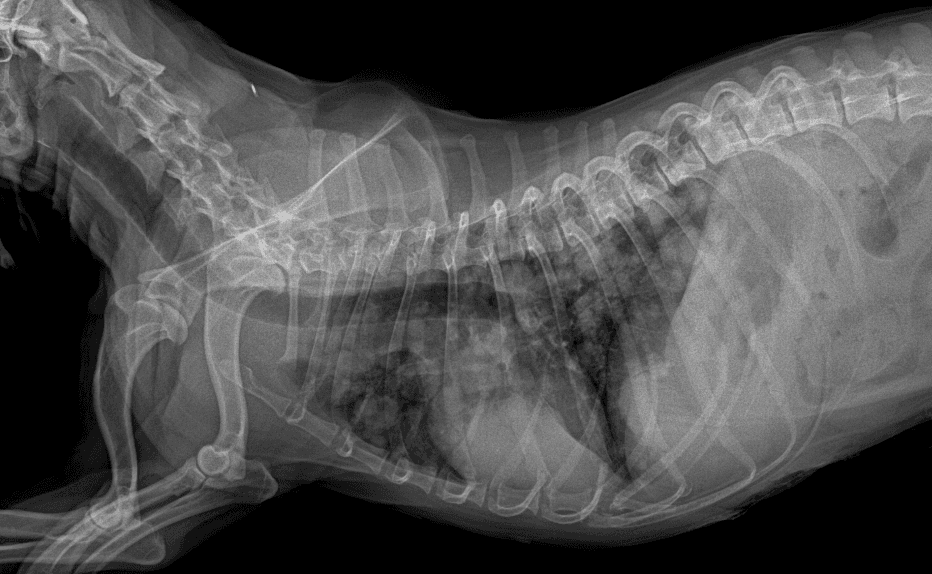

세부적으로 정형외과, 연부조직수술, 신장/혈액투석, 종양외과를 포함한 항암치료, 중환자치료센터, 그리고 진단영상센터로 구성되어 있습니다. 이러한 구성을 통해 중증질환의 치료시에 보다 발전된 진단및 치료방식으로 운영되도록 노력하고 있습니다.

호흡마취 시스템과 실시간 모니터링을 통해 안전한 마취가 가능합니다.

환자의 상태를 종합적으로 판단하여 수술을 진행합니다.

수술의 연장선상에 있는 재활 역시 최선을 다합니다.